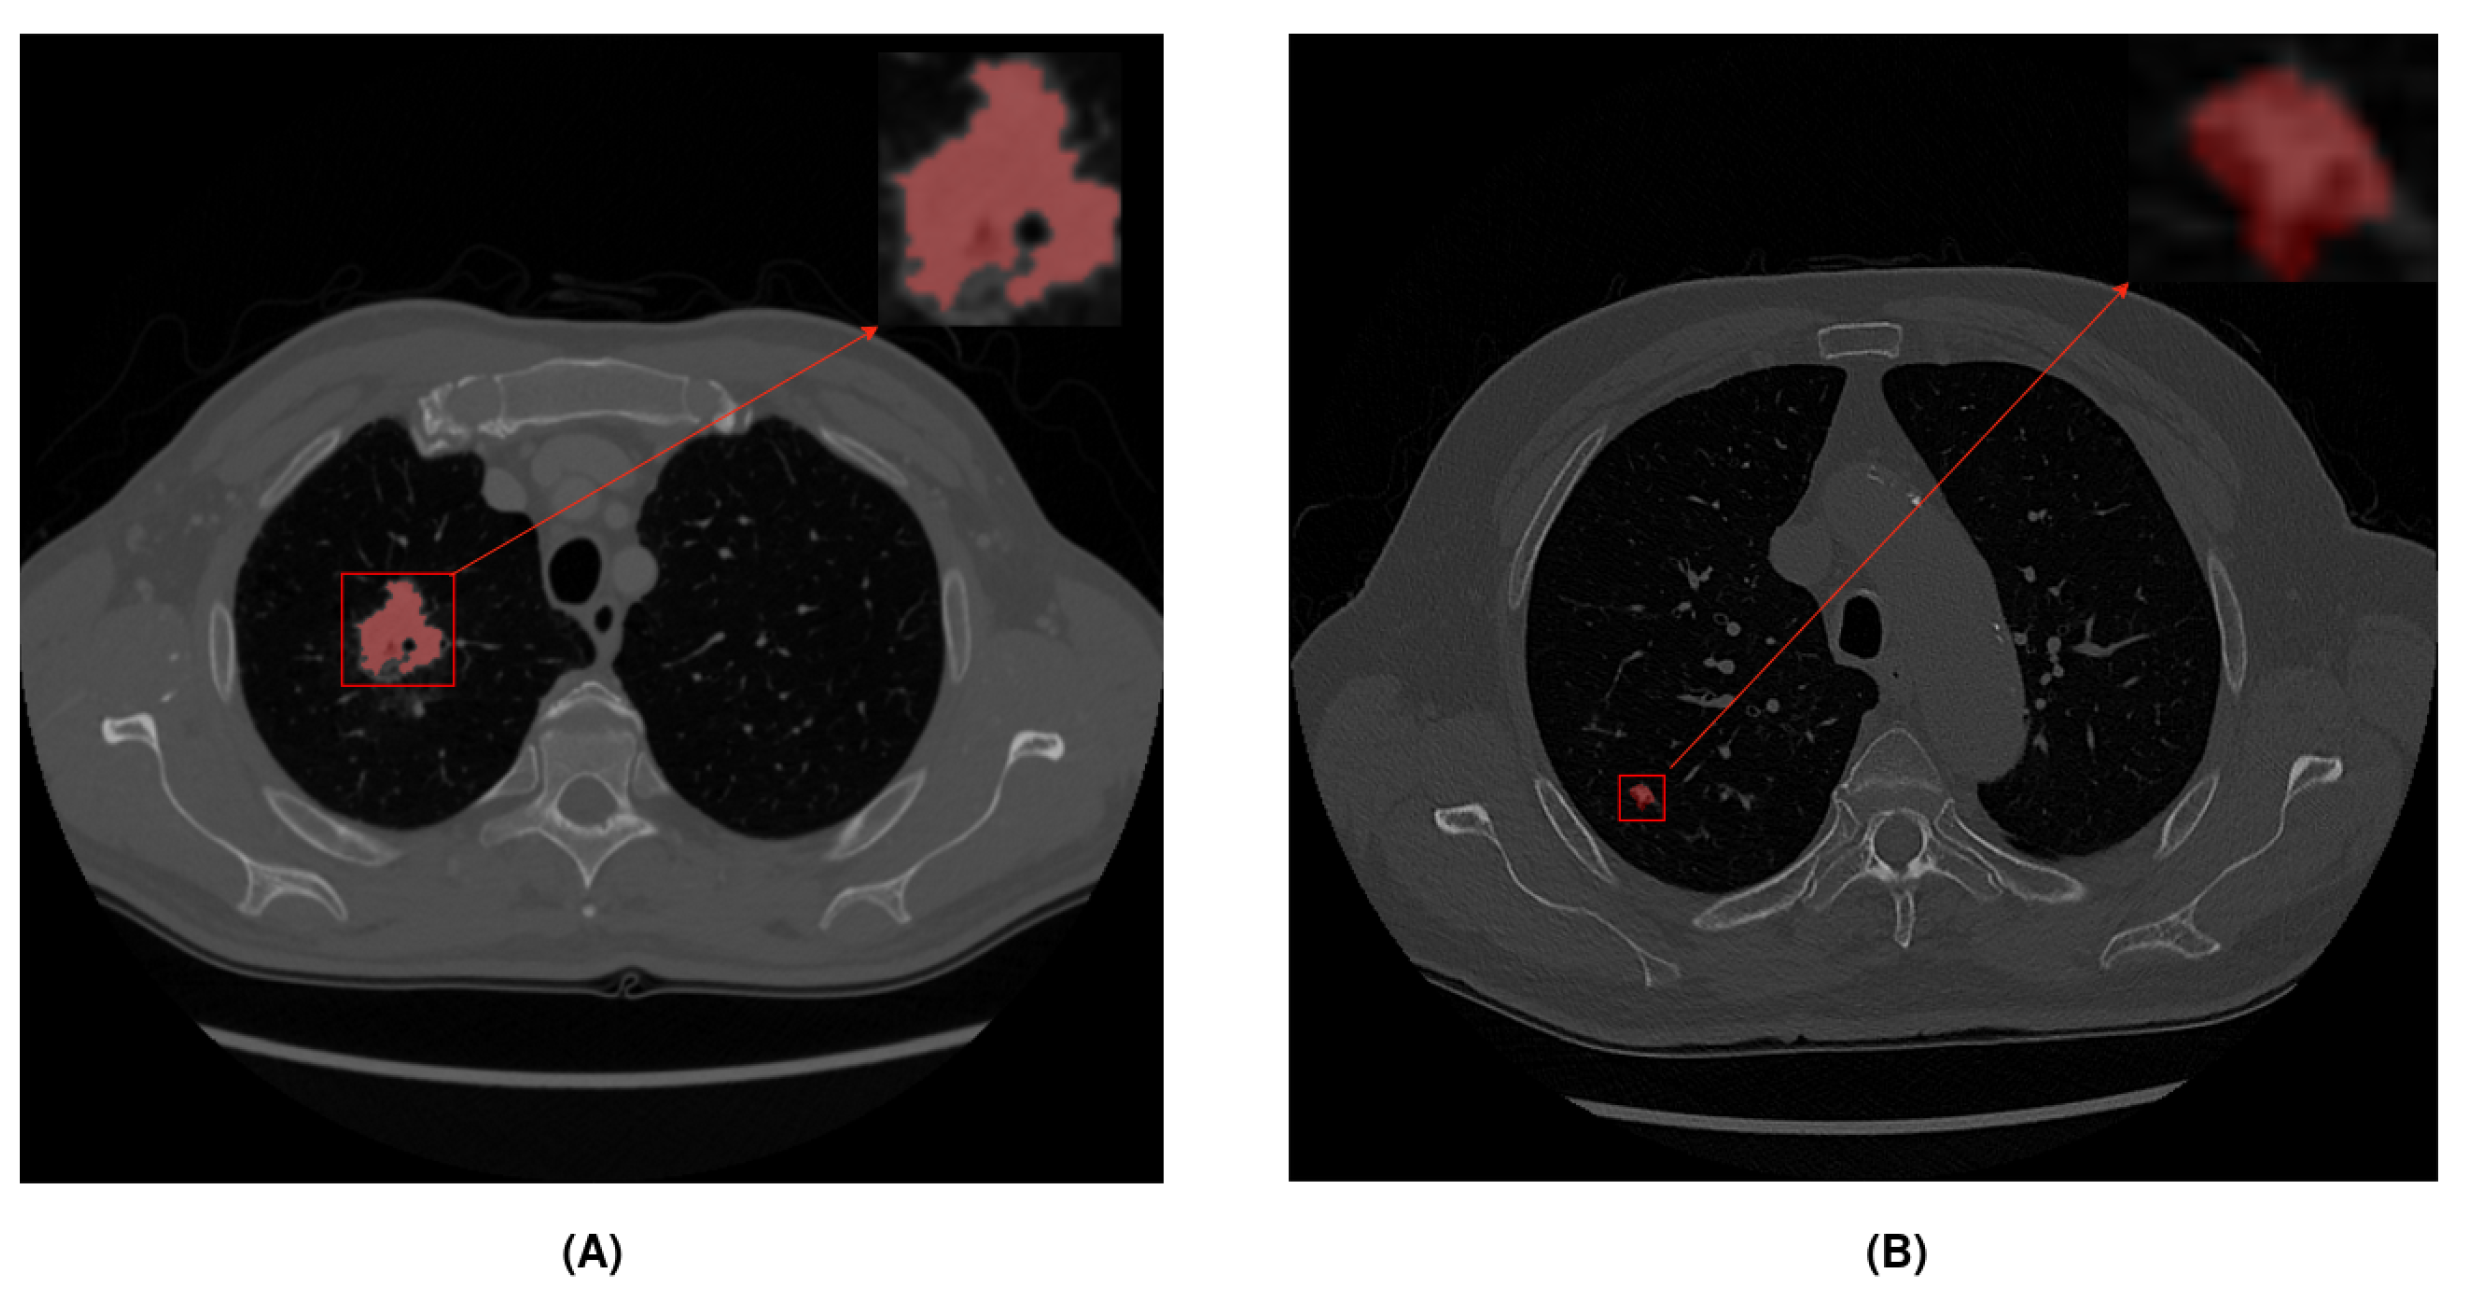

The UniToChest dataset [24] consists of about 300 k CT scans of pulmonary nodules. This is the largest publicly available lung nodule dataset. Images were acquired in the DICOM format, and each scan with nodules included an image and mask, both of 512 × 512 size. For slices without nodules, there was no mask. The proposed dataset also contains a wide variety of images of different sizes compared to other public datasets. The nodule diameter range is between 1 and 136 mm. During this study, we used 22,713 CT scans with nodules. The dataset includes division of images into training, validation, and test sets. To study the influence of different nodule sizes, we created two subsets from the original dataset, while respecting the original training, validation, and test sets. These two nodule subsets corresponded to larger nodules that were more likely to be malignant (greater than 10 mm) and smaller nodules (less than 10 mm) that could develop cancer in the future. Figure 1 shows an example of a CT scan for each subset. Table 1 shows all the image divisions made and the number of images per split.

Figure 1. Different subsets according to nodule diameter size. Red color represents the nodule area: (A) Example of a large nodule (>10 mm). (B) Example of a small nodule (<10 mm).